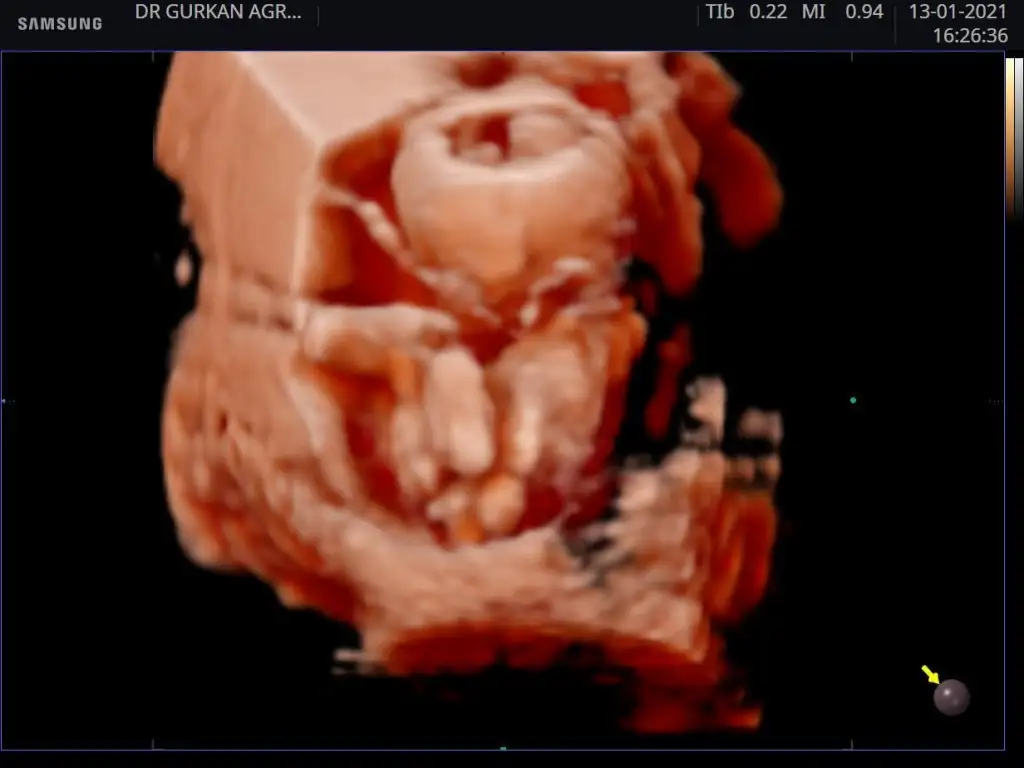

Bende bir kaç kişi diye baktırdım yorumları aynı bakalım sen ne diyeceksin kızkardeşimin 13 haftalık

13 haftalık doktor cinsiyeti söylemedi ama başkalarından tshmin aldim aynı cinsiyet i dediler bebek kardeşimin